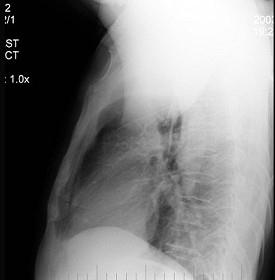

男性患者,52岁,体检胸片如图,最明确的是 ( )A.右上肺不张B.胸膜肥厚C.包裹性积液D.炎症E.支气管扩张

问题 男性患者,52岁,体检胸片如图,最明确的是 ( )

选项 A.右上肺不张 B.胸膜肥厚 C.包裹性积液 D.炎症 E.支气管扩张

答案 A